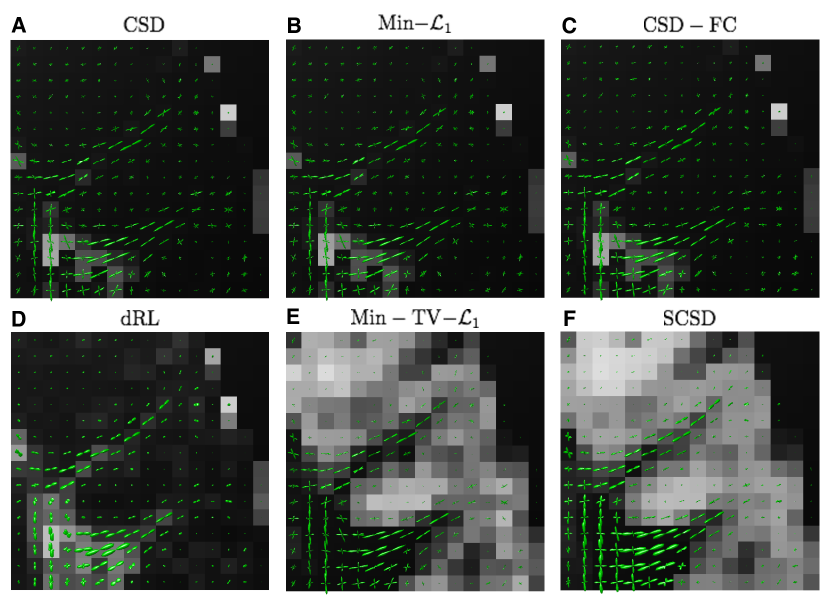

Fig. 10 depicts the reconstructions of fODFs obtained using the CSD (Subplot A), Min- (Subplot B), CSD-FC (Subplot C), dRL (Subplot D), Min-TV- (Subplot E), and SCSD (Subplot F) for the axial view and s/mm2. As opposed to Subplots A3-4 and B3-4 in Fig. 9, the fODFs in Fig. 10 are shown superimposed over the values of their corresponding IDMs. Analysing these results reveals the principal drawback of SD methods which disregard the effect of isotropic diffusion. In particular, not only CSD and Min- but also CSD-FC tend to yield spurious estimates of fODFs in anatomical regions corresponding to the cortical grey matter – the result which stands at odds with the fact that these regions are known to be devoid of neural fibre bundles. Further, although being capable of coping with the presence of isotropic diffusion, the dRL algorithm is “blending” and , which effectively impairs the angular resolution, and therefore the resolvability of crossing fibre tracts. Moreover, neither of the aforementioned methods has been found to be capable of reliably recovering the IDMs. At the same time, both Min-TV- and SCSD yield anatomically consistent reconstructions of the IDMs, with much less noisy results obtained in the case of SCSD. (This point is further illustrated by Fig. 11 which shows the “zoomed-out” IDMs recovered by the SD methods under comparison for the case of s/mm2.) Moreover, a closer inspection of Fig. 10 reveals that the fODFs estimated by means of SCSD are characterized by a smoother and more consistent spatial variability (owing to the fibre continuity constraint), thereby exhibiting a better adherence to the expected connectivity within an in vivo brain.